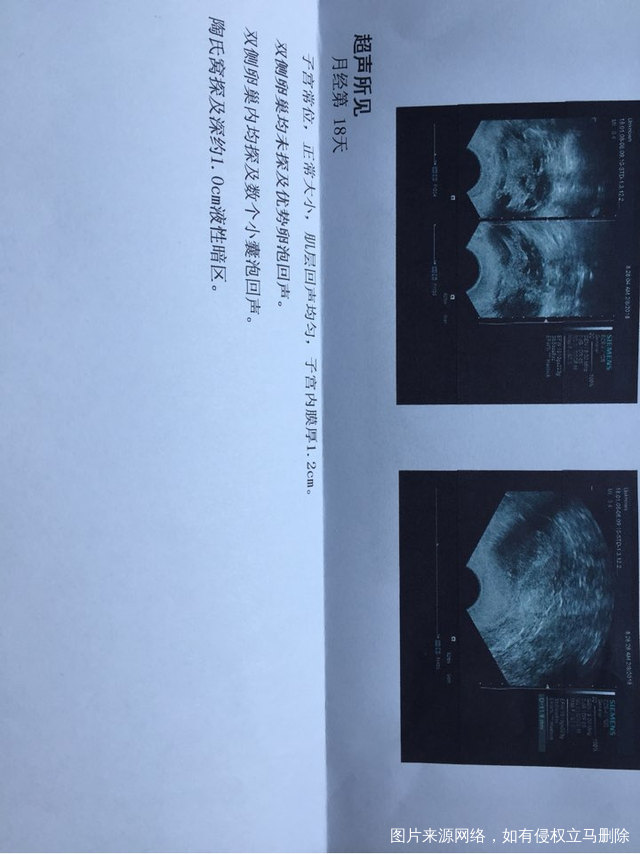

本人多囊卵巢,之前促排都不排卵,12月26做的造影,输卵管通畅,1月份没有管,2月4号检查自己长了卵泡,由于老公没在家,中间没有检查,今天8号去查已经排了,马上做了人工授精,医生说排卵不久,朋友们帮我看看有机会怀孕吗?盆腔积液1.0是排卵后多久